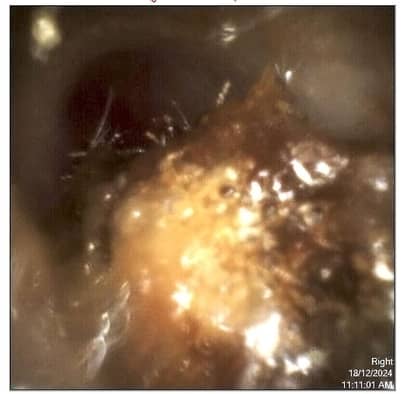

Microsuction is widely regarded as the gold standard for earwax removal, particularly for older adults and hearing aid users. It uses a fine suction tip under direct visualisation (with a microscope or video otoscope) to gently remove wax without introducing water into the ear.

Access to high-quality earwax removal has improved significantly across Australia. Many independent audiology clinics now offer microsuction and video otoscopy, allowing patients and caregivers to see precisely what is happening inside the ear.